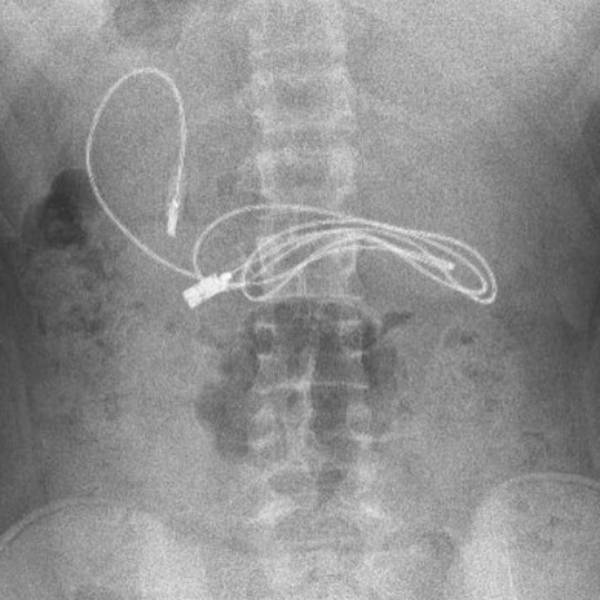

இதை ஏற்றுக்கொண்ட சிறுவனின் பெற்றோரும் எக்ஸ் ரே எடுக்க சம்மத்தித்தனர். இதன் படி எக்ஸ் ரே எடுத்து பார்த்ததில் சிறுவனின் வயிற்றுக்குள் மூன்று அடி நீளத்தில் சார்ஜிங் கேபிள் கிடந்தது மருத்துவர்களை அதிர்ச்சி அடைய வைத்தது. சிறுவனின் வயிற்றுப்பகுதிக்குள் இருந்த சார்ஜிங் கேபிளை உடனடியாக எடுக்க வேண்டும் என்று அறிவுறுத்தினர். இதன் பேரில் அருகில் உள்ள பிரட் பல்கலைக்கழக மருத்துவமனையில் சிறுவன் அனுமதிக்கப்பட்டான்.

எண்டோஸ்கோபி மூலமாக சிறுவனின் வயிற்றுக்குள் இருந்த கேபிள் அகற்றுவதில் சிக்கலான மருத்துவ நடைமுறைகள் இருந்ததாக டாக்டர்கள் கூறினர். கேபிளின் ஒரு முனை சிறு குடல் பகுதிக்குள் சென்றதால் எண்டோஸ்கோபி முறையில் அகற்றுவது மிகவும் கடினமானதாக இருந்தது என்று டாக்டர்கள் தெரிவித்தனர். மேலும் சிறுவனின் வயிற்றிற்குள் முடிகளை கட்டும் ரப்பர் பேண்டுகளும் இருந்ததாக மருத்துவர்கள் தரப்பில் கூறப்பட்டுள்ளது.